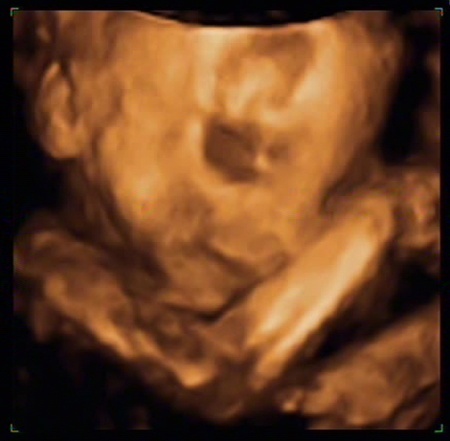

A szerdai 4D ultrahangon minden rendben ment, a választásom a kecskeméti kórházban is szonográfusként dolgozó és a terhességemet így végigkísérő Bérczi Ildikóra esett, ő végezte el az ultrahang vizsgálatot és úgy tűnik Koppi igazi férfi, Ildikó néninek mutogatja magát szívesen! Jó Békám, hozta a formáját, nem nagyon sikerült egy jól látható kukacos képet elkapni, de a két pici zacsi látszik és az is bizonyíték!

Ildikó hozzáértését eddig is sokan dicsérték, mint már mondtam, nem csak a mozizás miatt szerettem volna elmenni, nem csak azért, hogy láthassam és valóságosabbnak tűnjön a Pici számomra, hanem hogy megnyugodjak, minden rendben van. Koppány súlya 883 gramm, ami megfelel egy hasonló idős magzat átlag súlyának, viszont ami kicsit zavar, de megnyugtattak, hogy ettől még minden lehet rendben - mert felszívódhat -, mindkét veséjében találtak tágulatot.

Kisfiam már most lehengerli a hölgyeket, egy mosollyal ajándékozta meg a hálás közönségét is. Helyes pisze orra és szép telt szája van, ahogy nekem, apumnak és öcsémnek is. Fejvégű fekvésű és tényleg jól érzem, hogy állandóan a hólyagomba passzírozza magát. Illetve általában akkor, ha elmegyünk itthonról, míg itthon ülök vagy teszek-veszek, csak a szokásos mértékben kell mosdóba járnom. Ebből kifolyólag ismerem a megye, sőt amerre jártunk, az összes mellékhelyiséget. Szerencsére azt tapasztaltam, vidéken egyszerűbb normális állapotú mellékhelyiséget találni, ha már a szükség szólít, míg Pesten kihívás volt.